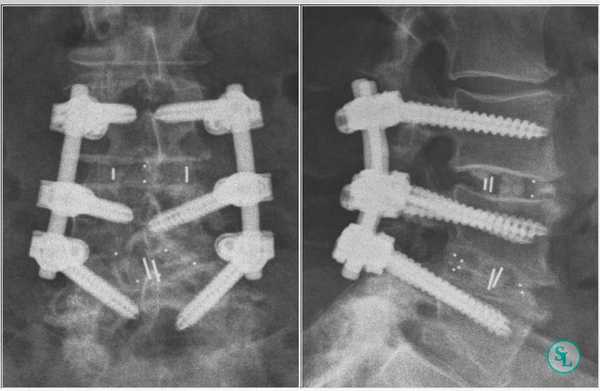

Перед установкой транспедикулярных винтов, на противоположной от резецированного сустава стороне, выполняется декортикация дуг, поперечных отростков для создания условий формирования спондилодеза. С помощью общепринятых анатомических и рентгенологических ориентиров выполняется транспедикулярная фиксация.

Траектория установки винта в аксиальной плоскости (а), проекция точки введения винта на задние отделы позвоночника (б), траектория установки винта в сагитальной плоскости (в).

Для введения транспедикулярных винтов используется наиболее доступная и распространенная методика freehand, однако требует от хирурга соответствующего мастерства. С целью более безопасного введения винтов и избежание их мальпозиции используется навигационное оборудование и интраоперационный нейрофизиологический мониторинг.

Последний этап транспедикулярной фиксации состоит в создании межтеловой компрессии при помощи специального инструмента и затягивания винтов. На ранее подготовленные декортицированные дуги и поперечные отростки выкладывается алло-или аутотрансплантат. Трансплантат используемый для создания спондилодеза можно смешивать с нативной смесью полученной в результате фильтрации интраоперационного отделяемого во время работы высокоскоростного бора. В конце операции выполняется рентгенологический контроль в 2-х проекциях.

Интраоперационная рентгенография поясничного отдела позвоночника после трансфораминального межтелового спондилодеза.

Для более прочной иммобилизации ПДС многие хирурги выполняют межтеловой спондилодез вместе с транспедикулярной фиксацией. Суть последней заключается в применении специальных конструкций, которыми дополнительно скрепляют тела позвонков.

Очень важно при установки винтов соблюсти следующие моменты: отсутствие пространства между костью и винтом, исключение травматизации нервных и сосудистых структур или смежных дугоотросчатых суставов. Импланты устанавливаются согласно размерной линейки каждого позвонка и винта, бикортикально не касаясь замыкательных пластин.

Размер закрепляющих винтов для каждого больного подбирается индивидуально. Различают моноаксиальные и полиаксиальные винты, также разработаны варианты с боковой фиксацией стержня. Они вводятся по конвергентной монокортикальной методике, подразумевающей перфорацию позвонка только в точке входа винта.

Винты изготавливаются из титана, что гарантирует их высокую стойкость к различным деформирующим нагрузкам. Они оснащены поверхностными колпаками, обеспечивающими стабильность положения конструкции и ее защиту от перекоса. Все винты установленной системы объединяются специальными пружинистыми металлическими механизмами, что равномерно перераспределяет нагрузку на них.